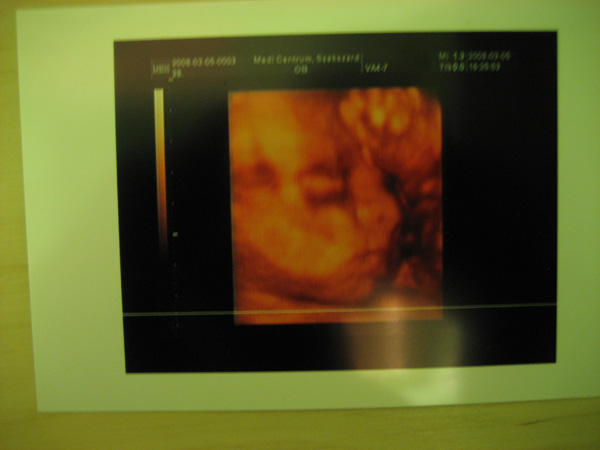

Kép Hát itt lenne a mi kis Mirkonk!

Remélem látszik.

Fej szélesség 7,52 cm

Fej körfogat 27,12cm

Has körfogat 26,22cm

Combcsont hossza 5,42cm

Mirko becsült súlya 1444g :shock: